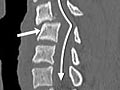

La tomografía computarizada (CT, por sus siglas en inglés) utiliza rayos X para obtener imágenes detalladas de la columna y las vértebras.

La tomografía computarizada (CT, por sus siglas en inglés) utiliza rayos X para tomar imágenes detalladas de la columna vertebral y las vértebras del cuello (columna cervical), la parte superior de la espalda (columna torácica) o la parte baja de la espalda (columna lumbosacra).